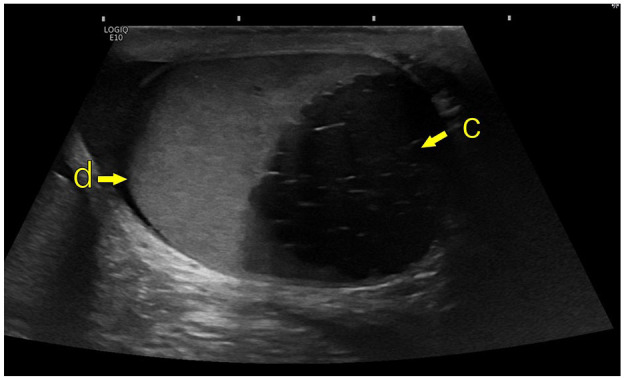

简介:Zinner综合征(ZS)以单侧肾脏发育不全、同侧精囊囊肿和射精管梗阻为特征。虽然罕见,泌尿科医生可能会遇到在他们的临床实践的某些点。文献主要局限于病例报告,对病情了解甚少。我们的目标是报告在两个中心管理的ZS病例,以便获得对这种情况的进一步临床见解。方法:对2021年1月至2024年6月期间在挪威西部两个中心出现的ZS病例进行回顾性分析。收集了有关人口统计学细节、症状学、影像学发现、管理和生育结果的数据。结果:6例患者符合ZS的全部三联征,年龄18 ~ 70岁。5例患者在出现症状时,报告诸如性活动中射精和睾丸疼痛等问题。两例急诊,一例急性尿潴留,另一例严重盆腔疼痛。半数患者采用保守治疗成功。三分之二的人通过自然受孕或辅助生殖方法生了孩子,而其余的人则接受了精子冷冻保存。结论:ZS表现出广泛的症状和不同的年龄。并非所有有症状的病例都需要手术干预,治疗应个体化。在某些情况下,保守的方法是可行的。

Introduction: Zinner syndrome (ZS) is characterised by unilateral renal agenesis, ipsilateral seminal vesicle cyst and obstruction of the ejaculatory duct. Although rare, urologists may encounter it at some point in their clinical practice. The literature is largely limited to case reports, and the condition is poorly understood. Our objective was to report on cases of ZS that have been managed at two centres in order to gain further clinical insights on this condition.

Results: Six cases were identified that met the full triad for ZS, with ages ranging from 18 to 70 years. Five patients were symptomatic at presentation, reporting issues such as anejaculation and testicular pain during sexual activity. Two cases presented as emergencies, one with acute urinary retention and the other with severe pelvic pain. Half of the patients were successfully managed with a conservative approach. Two-thirds had children, either through natural conception or assisted reproductive methods, while the remaining patients underwent sperm cryopreservation.